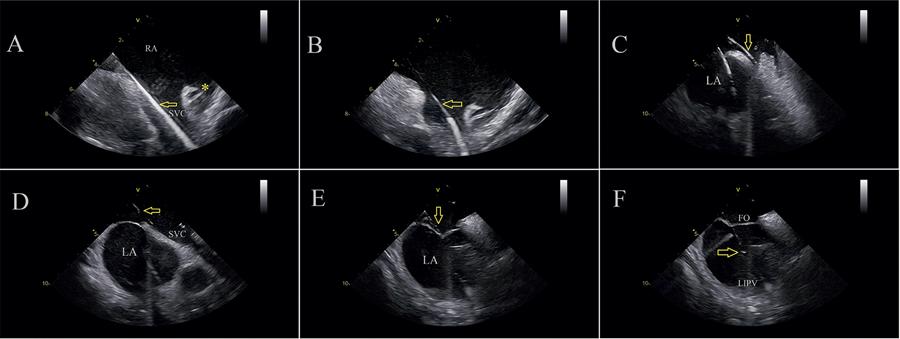

Avaliar a segurança e a eficácia aguda da ablação por cateter para tratamento da fibrilação atrial (FA) e arritmias supraventriculares (SVTs), utilizando uma abordagem exclusivamente não fluoroscópica, guiada por eco intracardíaco (ICE) e mapeamento 3D.

O isolamento das veias pulmonares (VPs), bem como todos os outros alvos que precisavam de ablação em ambos os átrios, foram alcançados e adequadamente visualizados. Não foram observados derrames pericárdicos, complicações trombóticas ou outras intercorrências nesta série. Punções transseptais difíceis (19 pacientes – 20%) foram realizadas sem fluoroscopia em todos os casos. Não foi utilizada fluoroscopia de backup, e nenhum vestuário de chumbo foi necessário. Avaliações detalhadas dos marcapassos após o procedimento não mostraram nenhum dano aos eletrodos, deslocamentos ou mudanças de limiar.

Uma estratégia de ablação por cateter sem uso de radiação para FA e outras arritmias atriais é segura e eficaz quando guiada pela utilização adequada do ICE e do mapeamento 3D. Diversos sítios em ambos os átrios podem ser alcançados e adequadamente ablacionados sem a necessidade de fluoroscopia de backup. Não foram observadas complicações. (Arq Bras Cardiol. 2020; 114(6):1015-1026)